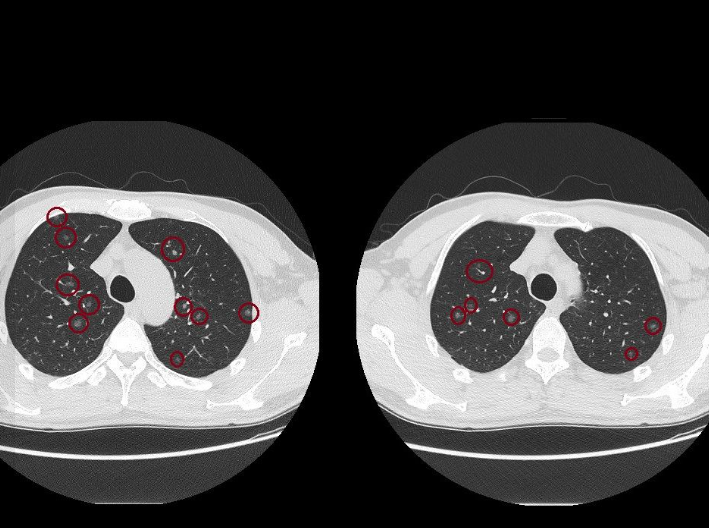

▲肺部有上百顆肺結節。(圖/翻攝自臉書/蘇一峰)

影像顯示,其肺部呈現「滿天星」狀態,布滿上百顆肺結節,且其中九成五以上皆為高風險的毛玻璃肺結節。

蘇一峰直言,面對如此密集的肺結節,臨床上根本無法單靠傳統開刀手術全數清除,後續追蹤與治療評估極具挑戰性。